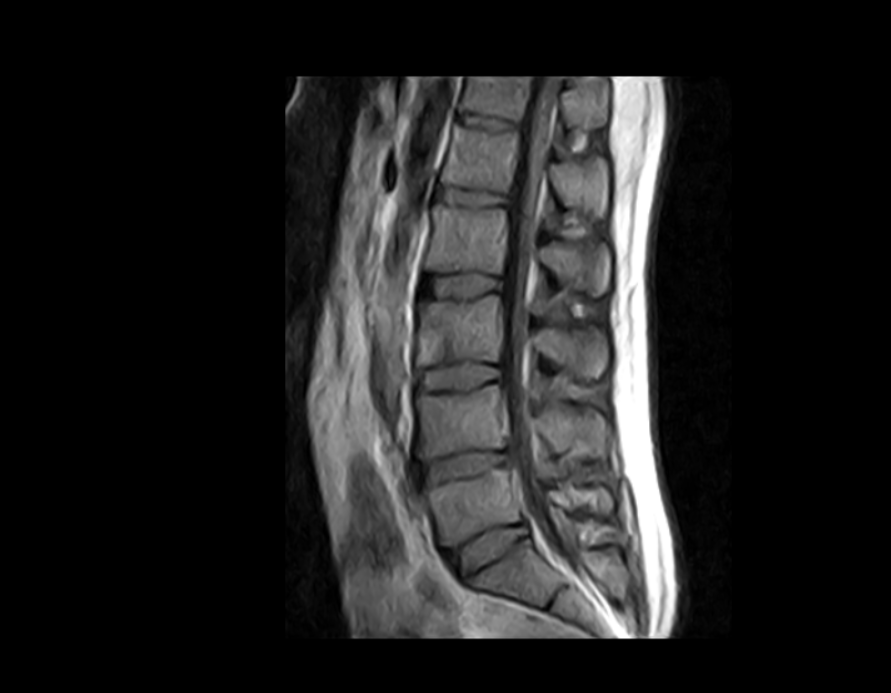

Esaote ha diseñado el sistema S-scan, que incluye la tecnología eXP, un escáner de resonancia magnética optimizado que cubre toda la anatomía musculo esquelética, desde el pie hasta los hombros, pasando por los segmentos más importantes de la columna, como la columna lumbar y cervical.

Imágenes Clínicas

El S-scan permite resonancias magnéticas cerebrales gracias a su amplia gama de aplicaciones a través de bobinas dedicadas.